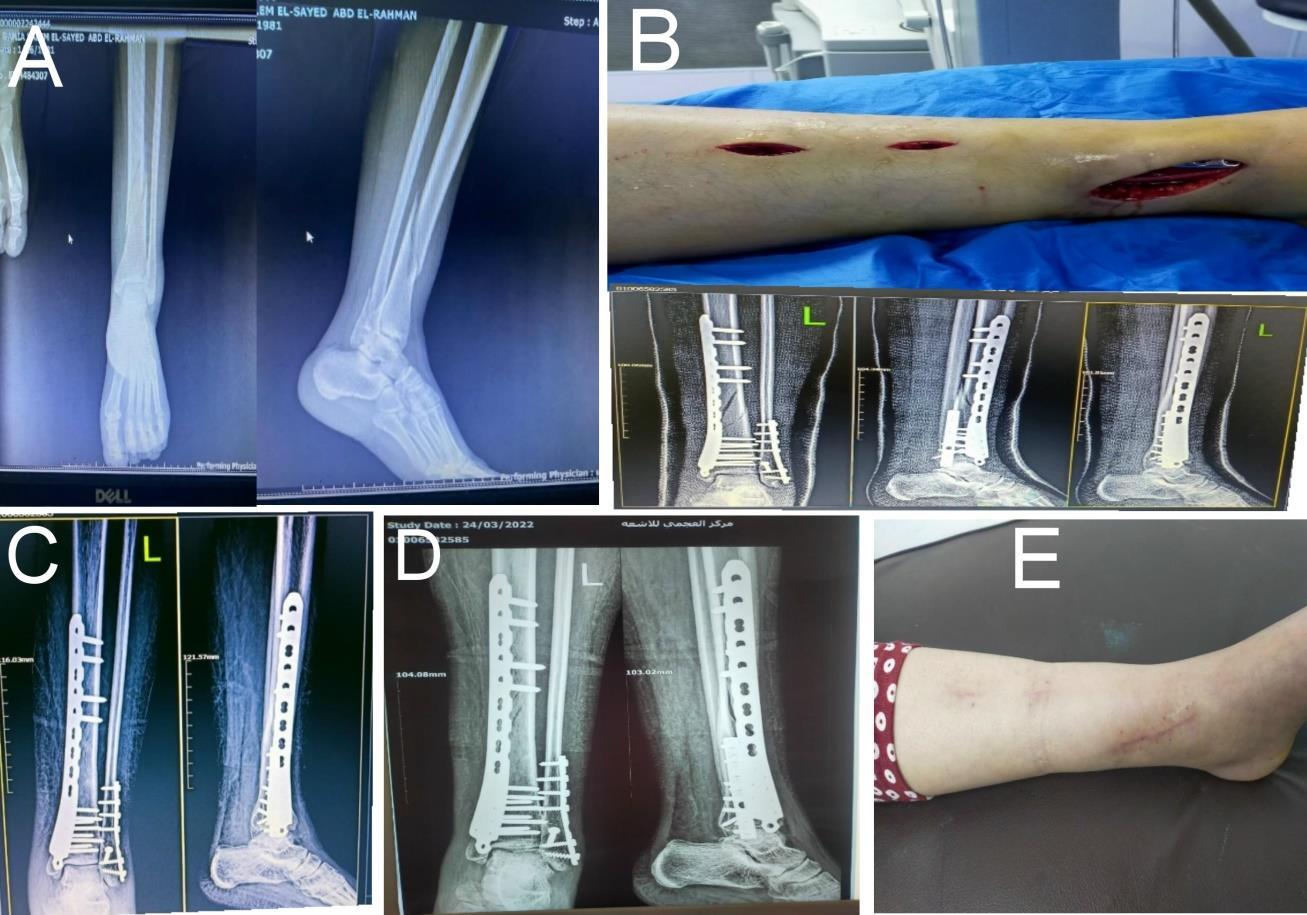

Case 2: Male patient 20 years old was presented by trauma due to road traffic injury to the right leg with associated fracture fibula. His result was excellent according to ankle hindfoot scale (Fig. 2).